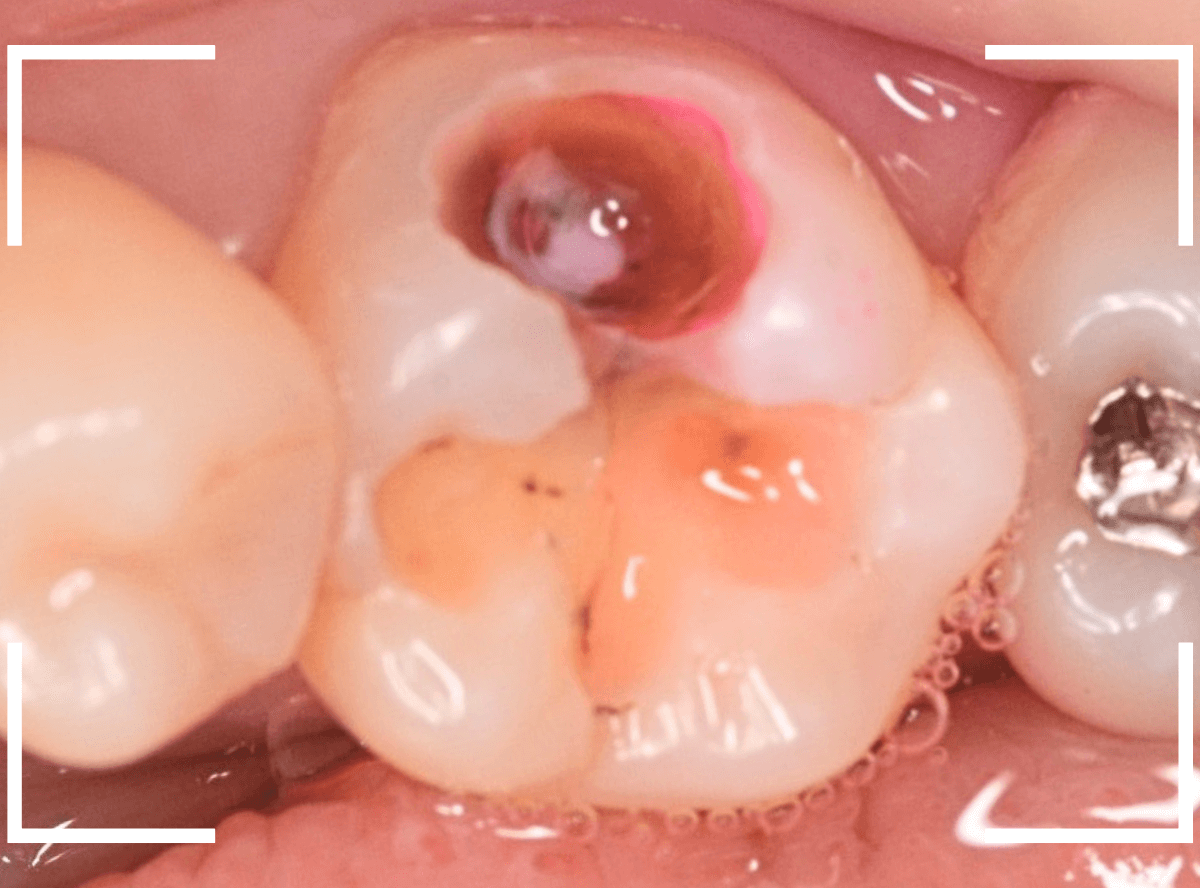

Case.16 金属の周りであちこちから虫歯

検診を希望された患者さんのケースです。

お口の中を拝見すると、上の奥歯の歯のすき間(隣接面)や、変色したレジンの中が怪しい感じです。

レントゲン写真で確認します。

青い線が神経で、赤い線が虫歯と思われる部分です。

奥から3歯が虫歯と思われますが、特に中央の歯の虫歯が深そうです。

まず、中央の歯の金属を除去します。

〇部分は前の治療時にしいたセメントです。この下に虫歯が広がっていると思われます。

セメントを除去したところです。

赤く染め出されているところが虫歯です。

神経に近くなっていますので、診療に虫歯を除去します。

側面のレジンや隣の歯との間の虫歯も慎重に除去します。

かなり広く虫歯が広がっています。

奥の歯の虫歯も全て除去しました。

3歯すべての虫歯を除去したところです。

しばらくお薬をつめて症状を経過観察した後、型どりをしてつめものを再製作する予定です。